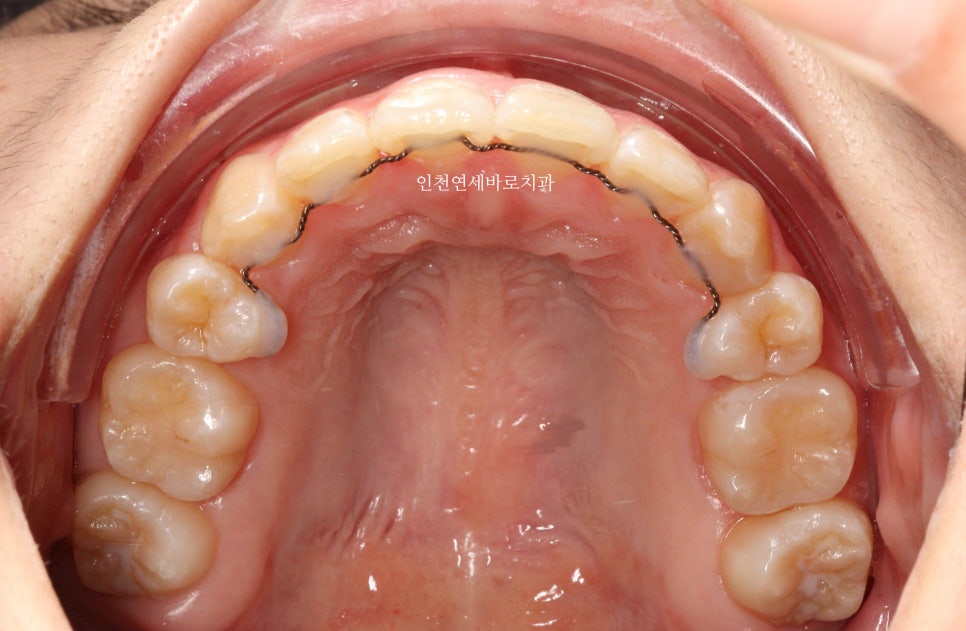

그리고 치료가 마무리 된 후의 모습입니다.

하지만 인비절라인은 전체교정에 준하는

치아와 주변조직에 무리가 되지 않는 범위에서의 확장을 만들어낼 수 있어

앞니의 뻗침을 최소화 할 수 있는 장점이 있습니다.

위 환자분의 재교정 치료기간은 약 7개월입니다.

7개월동안 병원은 두번 왔구요.